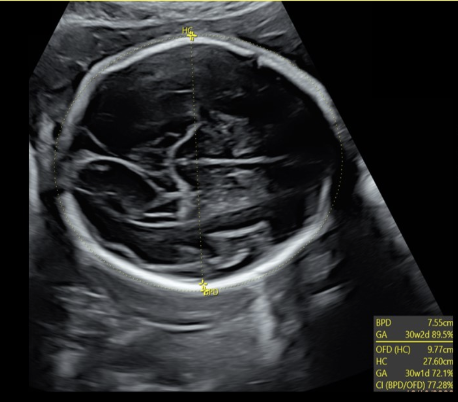

how to properly perform the occitpital-frontal (OFD) measurement of a fetus

.

a) coronal view of fetal head w/calipers placed from leading edge of the cranium

b) axial view of fetal head w/calipers placed from outer frontal edge to outer occipital edge of the cranium

c) axial view of fetal head w/calipers placed from the outer edge of one side of the cranium to the opposing outer edge of the cranium

d) axial view of fetal head w/calipers placed from side to side on outer edge of one side of the cranium to the opposing inner edge of the cranium

BPD measurements are taken from ____ edge of the skull to ___ edge of the skull

a) inner, inner

b) outer, inner

c) outer, outer

d) inner, outer

the correct cranial level for BPD + HC assessment is

a) Transverse axial view of the fetal skull at the level of the cavum septum pellucidum, third ventricle, and thalamus

b) Transverse axial view of the fetal skull at the level of the cerebellum and cisterna magna

c) Coronal view of the fetal skull at the level of the cavum septum pellucidum, third ventricle and thalamus

d) Transverse axial view of the fetal skull at the level of the lateral ventricles and choroid plexus